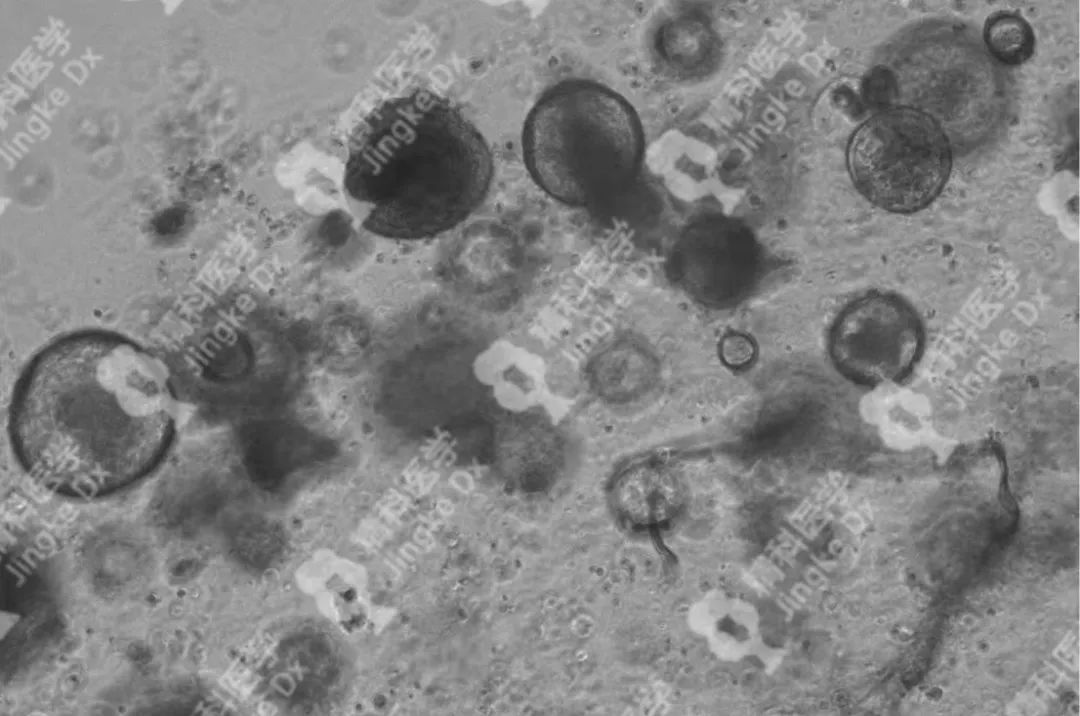

PIC.02

精科宮頸癌類(lèi)器官圖像